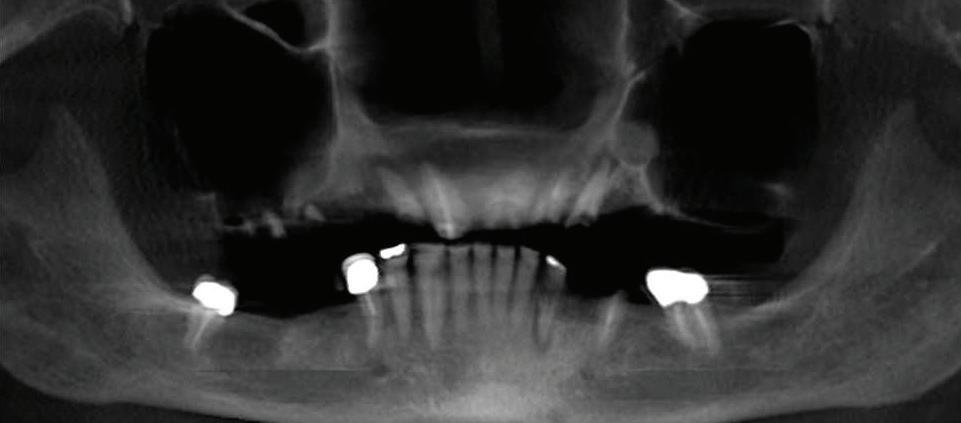

Face The Future

Can just four implants replace all of the teeth on the top or the bottom of your mouth? Thanks to advances in dental implant technology, that answer is a resounding yes.

Tooth loss is extremely common among adults, especially as we age. Rather than living with the discomfort and hassles of dentures, many people are opting for what is called “all-onfour” dental implant restoration.

An implant is a small titanium screw

that fits inside your jawbone and replaces the root-part of a missing tooth. Minor surgery is required to insert the implants. Once the implant is in place, a crown is attached to give you a highly realisticlooking and functional prosthetic tooth. You do not need a dental implant for each and every one of your missing teeth. All you need is four precisely placed implants on the top of your mouth, and four on the bottom, to restore your full smile. That’s the beauty of the all-on-four. And because the implant is made of titanium, it has the unique ability to fuse to living bone and function as part of it. So eventually, the dental implant becomes part of the jawbone and serves as a strong, long-lasting foundation for your new teeth.

Besides ensuring that your implants are permanently fixed in place, this bone fusion has another important benefit: it prevents future bone loss in the jaw. This helps to maintain a more youthful facial structure – and better oral health. But perhaps the biggest

Please see “All-On-Four,” page 61

301-805-6805 page 16 | Your HEALTH Magazine Since 1977, AT HOME CARE, INC. has helped thousands of persons enjoy the pleasure and peace of staying at home. Your Care. Your Way. Our Services are designed to make life safer and more enjoyable: • Personal care and hygiene • Meal Preparation • Shopping • Light Housekeeping • Laundry • Activity and Appointment Assistance • Companionship • Medication Reminders • Exercise assistance Call today to discuss your personal situation. 301-421-0200 Visit us online at AtHomeCareInc.com All-On-4: Same Day Smiles CALL TODAY TO GET YOUR OLD SMILE BACK! 301.294.8700 Dental Implant Center of Rockville 77 South Washington Street, Suite #205 Rockville, MD 20850 • www.DrSreeni.com Courtesy 3D Planning For Implants When patients bring a 3D scan with them to or have one taken in the office. Appointment needs to be scheduled before July 15, 2024 Missing Teeth or Tired of Wearing Dentures? Thanks to advances in dental implant technology, just four implants can replace all of the teeth on the top or the bottom of your mouth. All-On-Four Dental

Implants